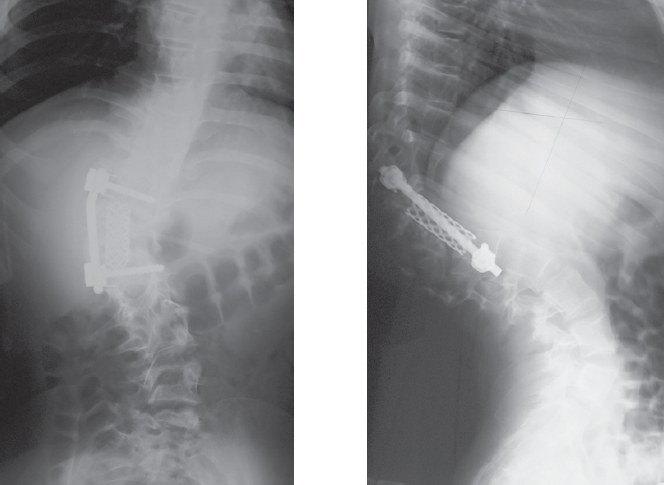

Clinical case of surgical treatment of advanced congenital kyphoscoliosis in 12 years old child is reported. Radiographs and CT at presentation failed to reveal the entire anomaly. By analysis of priorly made radiographs hemivertebra L1 was recognized. At genitourinary assessment L-shaped kidney was detected. A full-size 3D-printed model was used for surgical planning. Vertebral column resection as treatment option was discussed, but due to high neurologic complication rate this approach was refused. After preoperative 35 days halo-femoral traction anterior instrumented fusion was performed. Right ureter was stented for intraoperative urologic injury prevention. Scoliosis correction of 32% and kyphosis of 14% was achieved. 5 months later definitive posterior uninstrumented fusion was performed. Spinal deformities caused by vertebral malformations progress dramatically unless they are treated early. An advanced case is a clinical challenge because of technical difficulties and poor result. Vertebral column resection is a treatment option for severe kyphoscoliosis, but it’s indications should be strictly individualized. Preoperative halo-femoral traction is the most safe correction method in spinal deformity due to prolonged and gradual action. 3d-printed models are practical for surgical planning. The model may be used intraoperatively as a 3D-reference. In congenital scoliosis genitourinary system should be assessed meticulously, and urologist advice in relevant case is necessary.